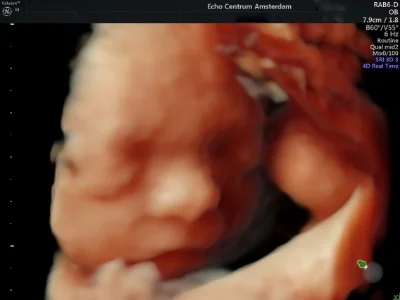

Vlinders in mn buik Wat een magisch moment toen we voor het eerst het gezichtje van ons kleine wondertje zagen, ze lachte en deed haar oogjes open, alsof ze naar ons gluurde. Dit is echt geweldig, nog helemaal aan het nagenieten. Ik kan iedere a.s. ouder Dr. papa aanbevelen.Hij geeft zeer heldere uitleg en heeft veel geduld en liefdevolle aandacht.

Vandaag onze nu al fantastische dochter gezien in 3 & 4D. Een magisch moment, want nu hebben we écht duidelijk beeld bij haar lieve, mooie snuitje en dat beweeglijke lijfje. Dat wat ik voelde is nu samengekomen met dat wat we van haar gezien hebben. Een waanzinnige ervaring! Heel veel dank dr. Papa, ook voor de heldere, begeleidende uitleg!

Al jaren hoorde ik vele goede verhalen van cliënten en collega's. Toen ik zelf zwanger was, wilde ik dan ook graag eens een echo bij drs. Papa mee maken. En ik begreep meteen waarom iedereen altijd zo enthousiast was! Via de (2,3 & 4D) echo van Elvin Papa maakten wij voor het eerst kennis met ons kindje. Dit was toch weer heel anders dan de standaard medische echo's die hieraan vooraf waren gegaan. Ik was ontroerd! Sinds deze echo voelde ik meer 'band' met ons ongeboren kindje. Wij zagen op de echo dat hij voortdurend zijn handjes voor zijn gezicht hield en Elvin voorspelde dat wij dit vast terug zouden zien als hij eenmaal in de wieg lag. En ja hoor, nu onze zoon er is herkenden wij onmiddellijk zowel het gezichtje, als de handjes voor het gezicht waar hij erg aan verknocht lijkt. Zo mooi! Verder vonden wij het heel prettig dat zo'n deskundig en vriendelijk persoon als Elvin alle items van de 20 weken-echo nog eens bekeek en in begrijpelijke taal aan mijn man, (schoon)moeders en mij toelichtte. Ik kan het al mijn cliënten aanraden!